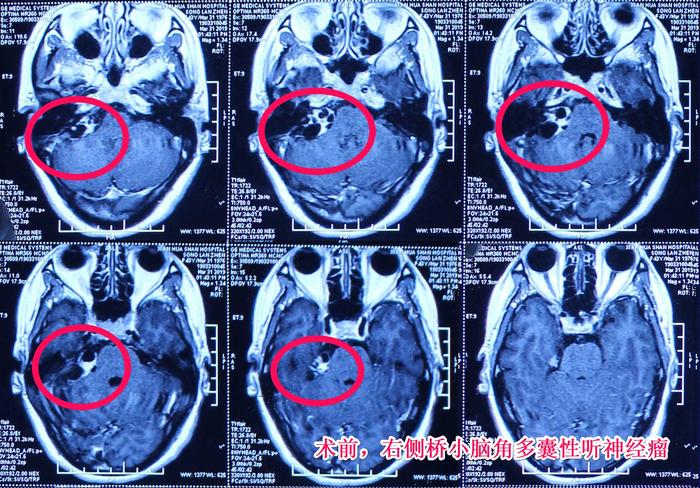

病例分享高难度多囊性听神经瘤病例分享

图片尺寸700x488